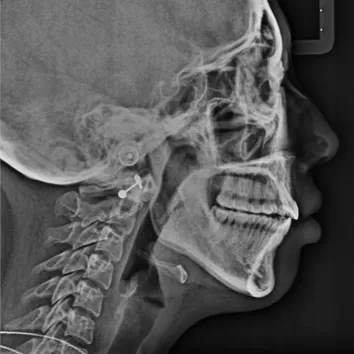

Rayons X avant le traitement

[Radiographie panoramique/Céphalogramme latéral]